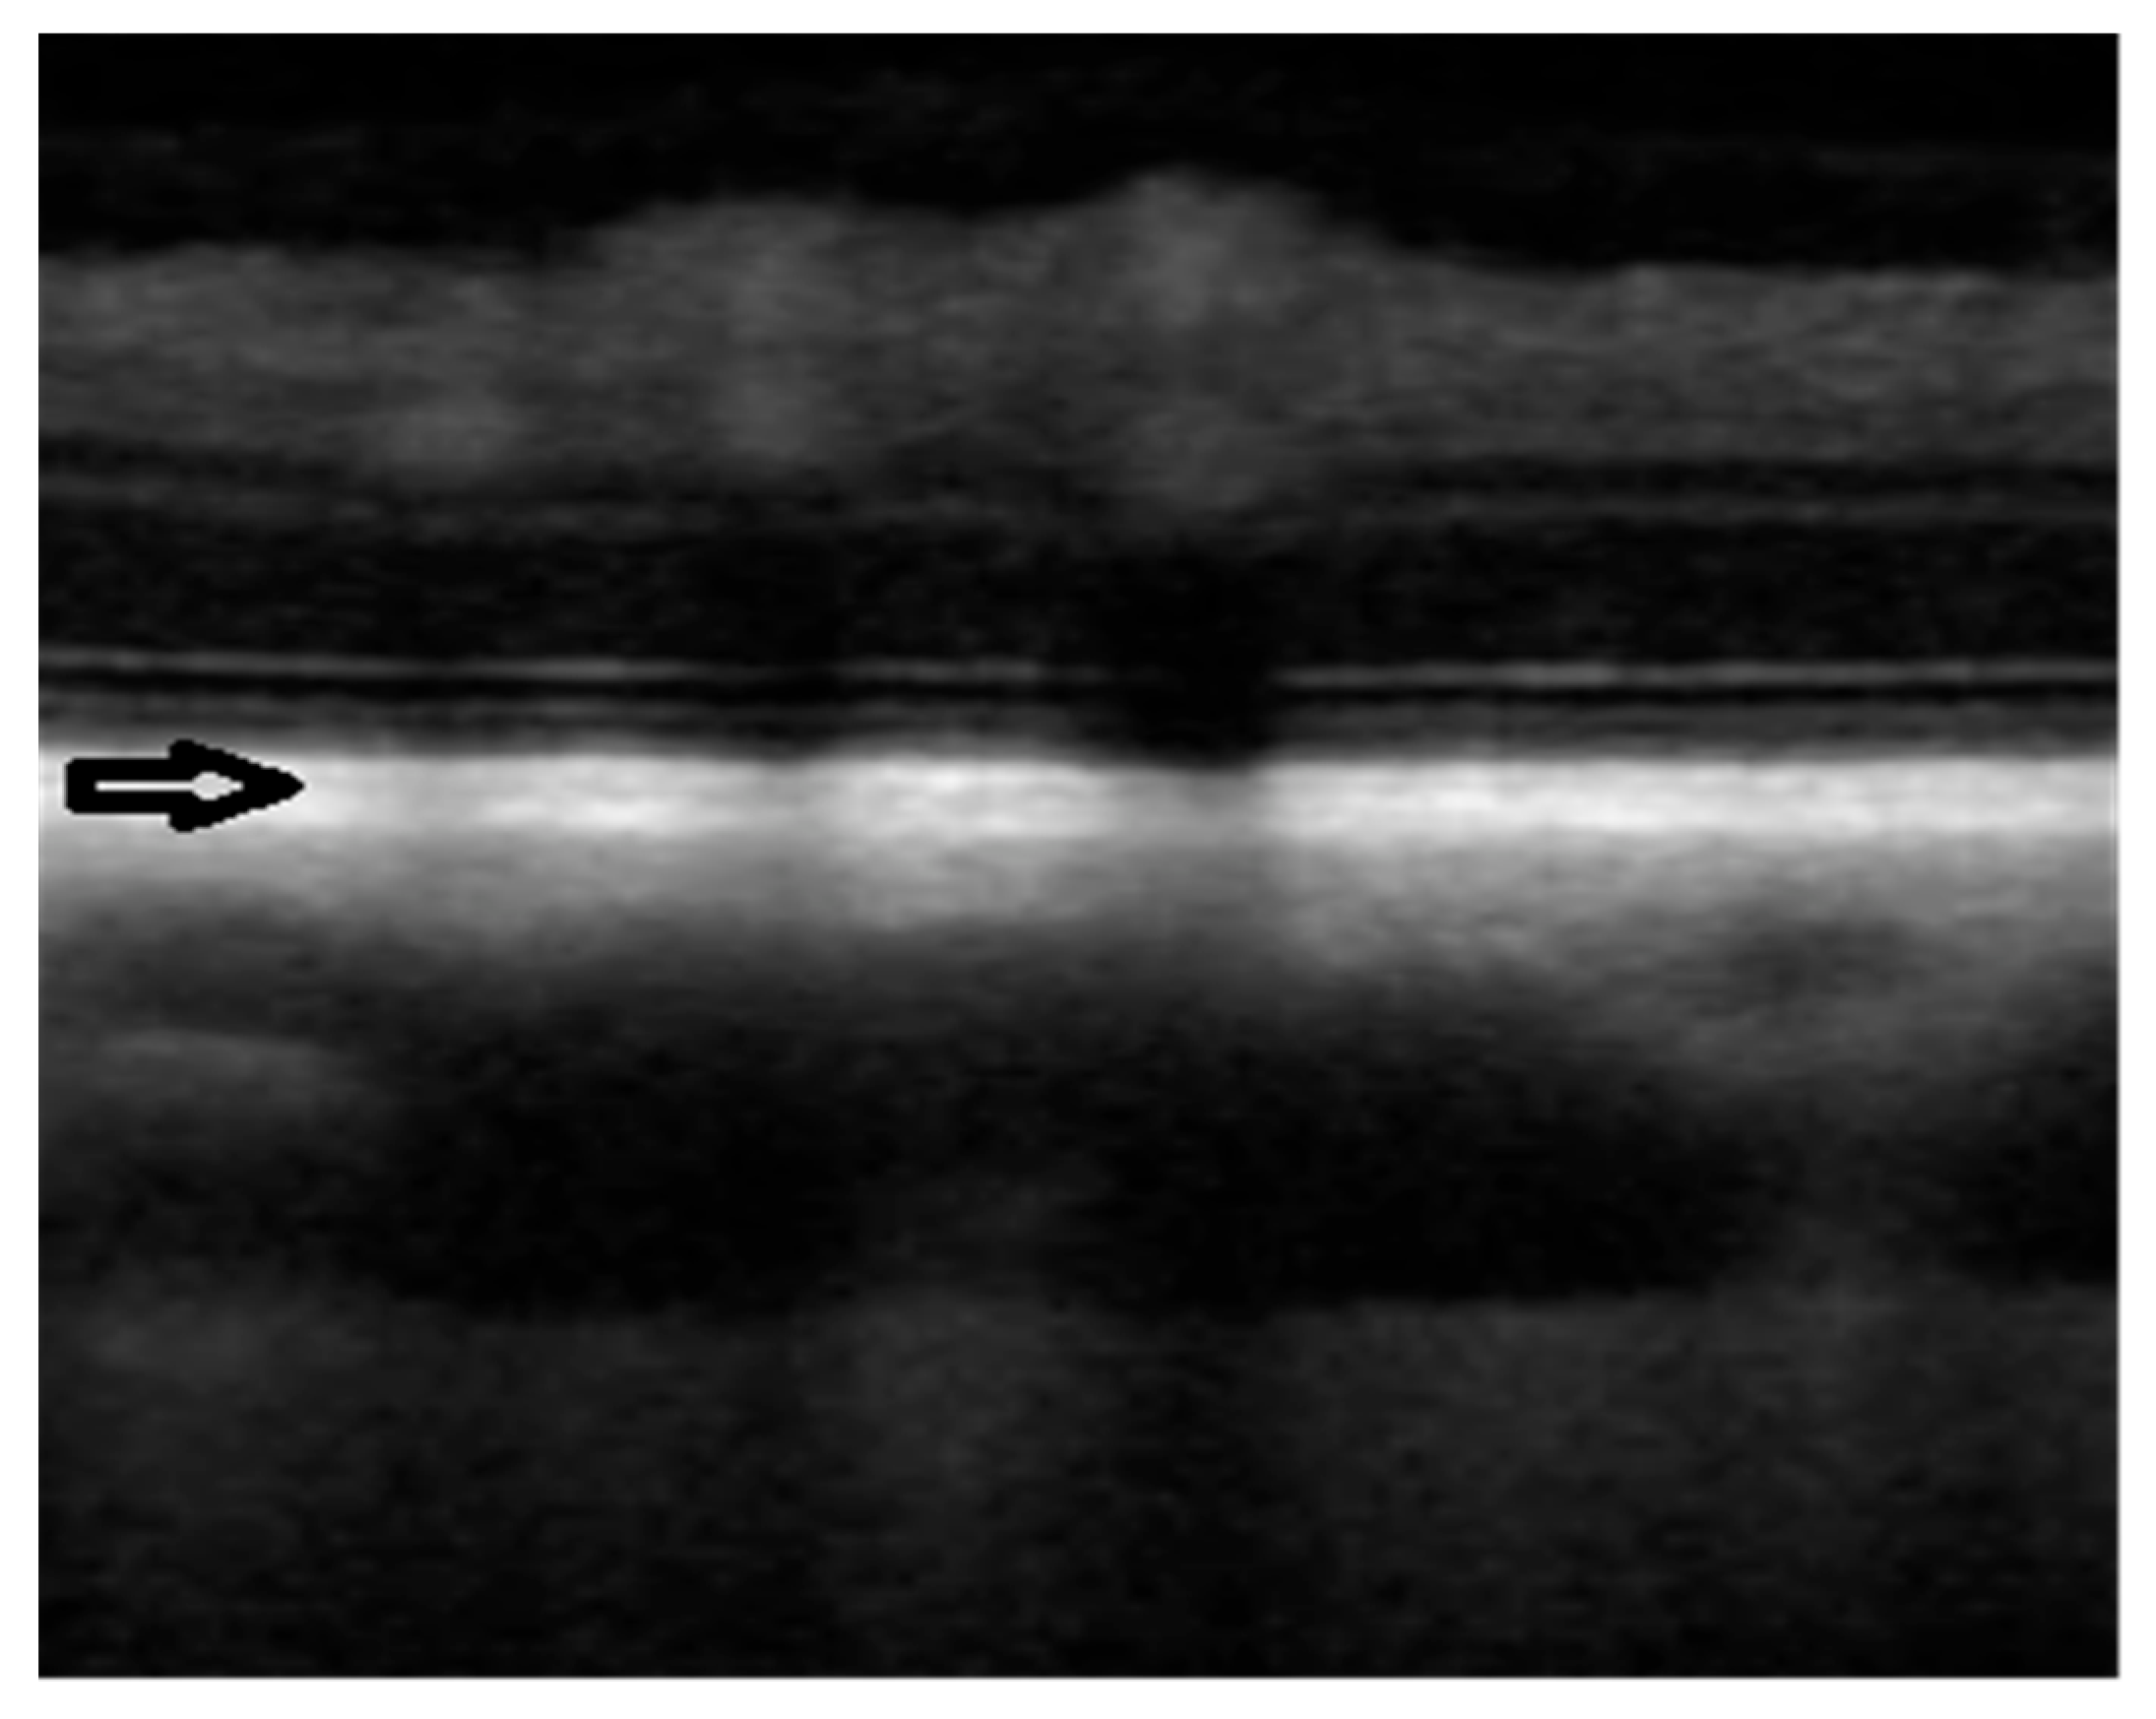

- Yamaue, Y.; Hosaka, Y.Z.; Uehara, M. Macroscopic and Histological Variations in the Cellular Tapetum in Dogs. J. Vet. Med. Sci. 2014, 76, 1099–1103. [Google Scholar] [CrossRef]

- Lesiuk, T.P.; Braekevelt, C.R. Fine Structure of the Canine Tapetum Lucidum. J. Anat. 1983, 136, 157–164. [Google Scholar]

- Soukup, P.; Maloca, P.; Altmann, B.; Festag, M.; Atzpodien, E.-A.; Pot, S. Interspecies Variation of Outer Retina and Choriocapillaris Imaged With Optical Coherence Tomography. Investig. Ophthalmol. Vis. Sci. 2019, 60, 3332–3342. [Google Scholar] [CrossRef]

- Mischi, E.; Soukup, P.; Harman, C.D.; Oikawa, K.; Kowalska, M.E.; Hartnack, S.; McLellan, G.J.; Komáromy, A.M.; Pot, S.A. Outer retinal thickness and visibility of the choriocapillaris in four distinct retinal regions imaged with spectral domain optical coherence tomography in dogs and cats. Vet. Ophthalmol. 2022, 25, 122–135. [Google Scholar] [CrossRef]